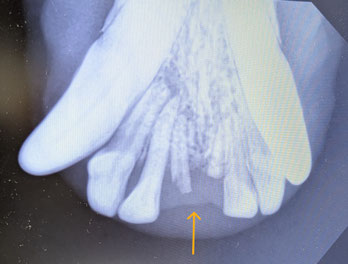

📸 レントゲンでの確認

レントゲン写真では、

歯ぐきの中に折れた歯の根が残っている様子が確認できます。

このように、見た目では問題がなくても、

内部で炎症が進行している場合があるため、歯科レントゲン検査が非常に重要です。

特に、「歯が折れたあと何もしていない」「一部が欠けたまま」の場合は、

中で歯根が残っていることがあります。